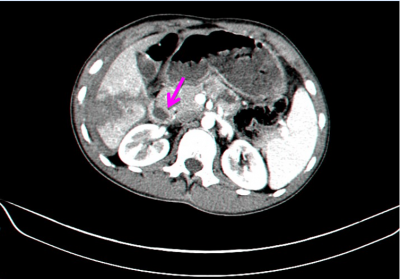

- טומוגרפיה ממוחשבת - בדיקה זו יכולה להראות את היקף הנזק ומיקומו. בדיקה זו אפשר לבצע בחולים שהם יציבים המודינמית, והיא בדיקת הבחירה (תצלום 7.10 ). ניתן להדגים גם דימום פעיל מהכבד על ידי הדגמת דליפה של חומר ניגוד באזור החבלה (תצלום 8.10).

בנוסף ב- CT אפשר לראות גם פגיעות באיברים אחרים (תצלום 9.10) כולל כלי דם (תצלום 10.10).